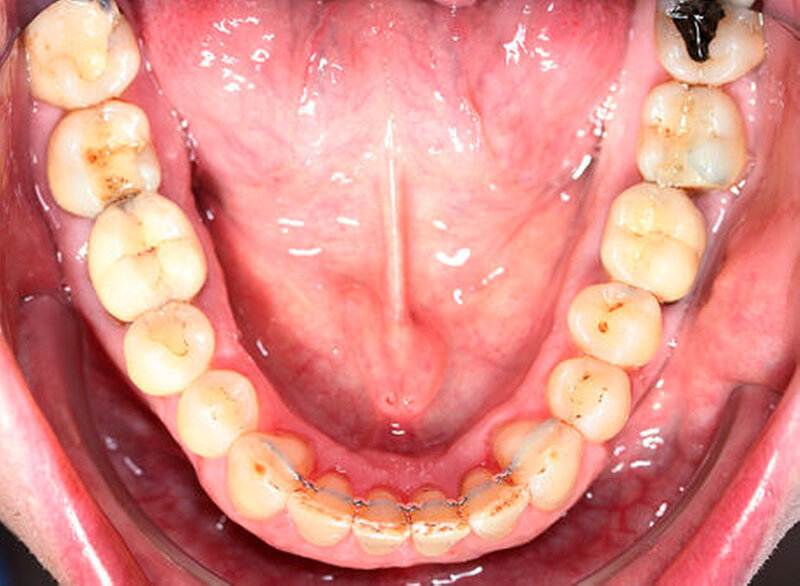

Anamnestisch lagen keine Besonderheiten vor. Es ist jedoch zu vermerken, dass ein regelmäßiger Alkohol-, Koffein- und Nikotinkonsum zugrunde lag. Intraoral zeigte sich ein bereits konservierend versorgtes permanentes Gebiss mit aktivem und inaktivem kariösen Geschehen. Große Anteile der Zahnhälse lagen nach Zahnfleischrückgang in Kombination mit Knocheneinbrüchen frei. Zahn 27 wurde bereits extrahiert.

Eine Beurteilung der parodontalen Situation an Zahn 11 offenbarte mesial und distal Sondierungstiefen von jeweils 6 mm.

Kieferorthopädisch imponierte beidseits eine neutrale Verzahnung bei einem tiefen Biss von 5 mm – bedingt durch die Verlängerung beider Frontzahngruppen. Besonders Zahn 11 zeigte eine erhebliche Verlängerung und Protrusion mit einer sagittalen Frontzahnstufe von 5 mm. Sowohl die Frontzähne im Ober- als auch im Unterkiefer wiesen eine lückige Beziehung zueinander auf (Abbildung 1).